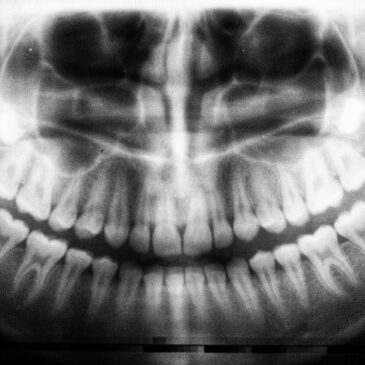

Where necessary, a physical examination will be supported by X-rays or advanced imaging techniques. Tissue or bone analysis may also be carried out, ensuring a comprehensive medical and aesthetic treatment plan is developed for you.